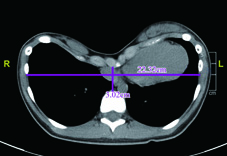

目前漏斗胸病人就診後首先都會照胸部X光片基本評估嚴重度,後續有可能會安排血液檢查、心電圖、肺功能檢查、心臟超音波檢查及胸部電腦斷層檢查。當內陷指數達一定程度,且評估手術的效果能改善到一定程度時,就會建議手術治療。

嚴重的漏斗胸,幾乎前胸貼後背